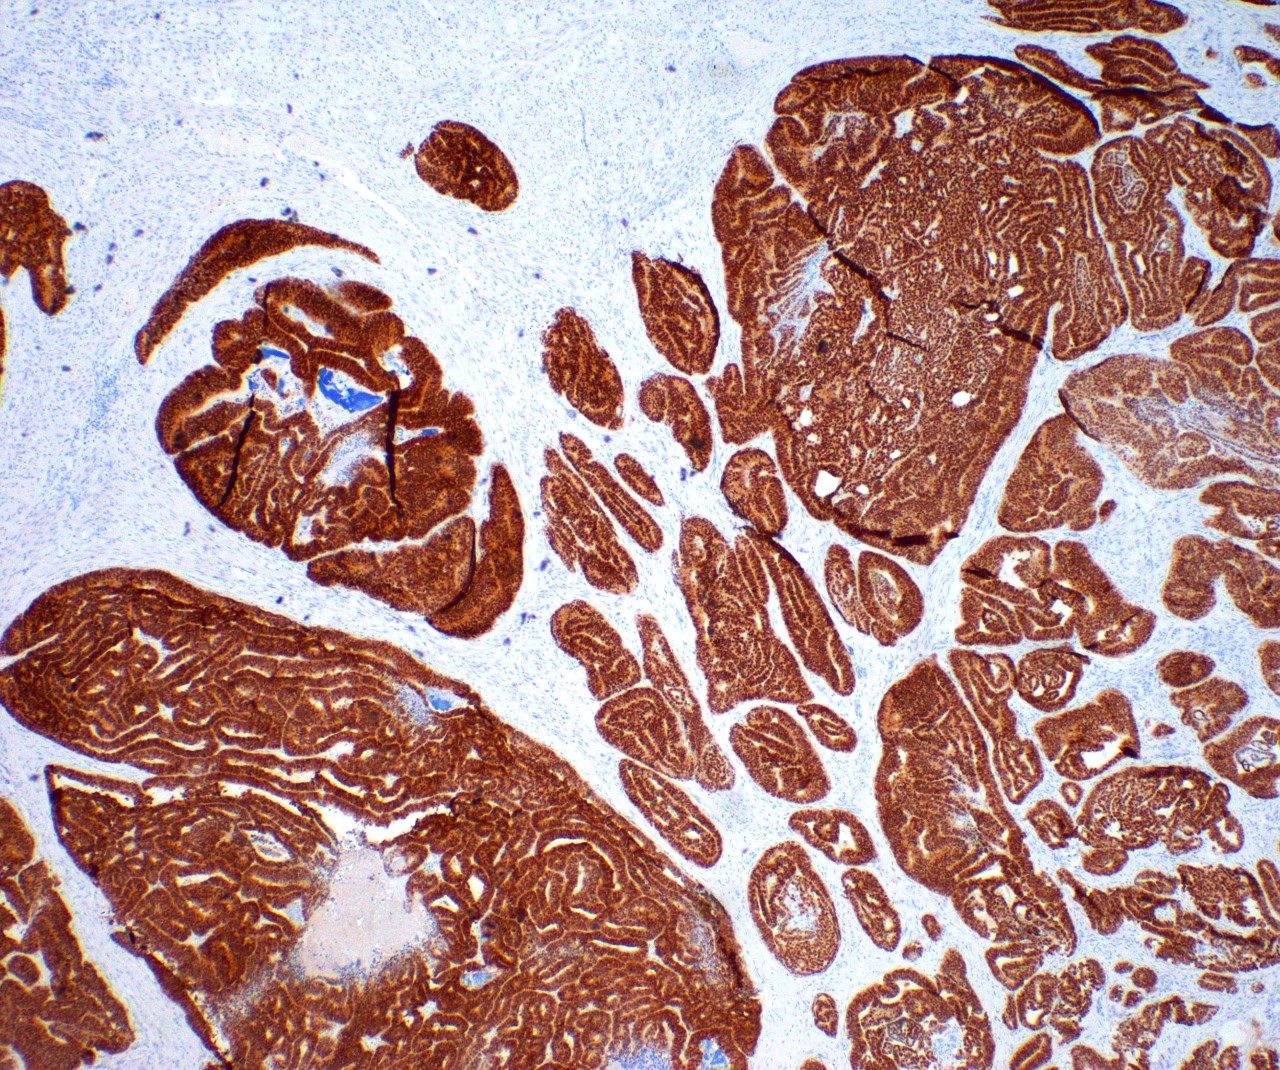

Microscopic (histologic) images

Contributed by Daniel Graham, M.D., Adele Wong, M.B., B.Ch., B.A.O. and Lucy Ma, M.D.

Positive stains

- PAX8: usually diffusely positive

- GATA3 and TTF1: focal or diffuse with inverse staining pattern described in several studies in the most recent WHO classification; cells positive for GATA3 are negative for TTF1 and vice versa (Am J Surg Pathol 2018;42:1596)

- CD10: focal and apical / luminal

- p53 wild type

- MMR proficient